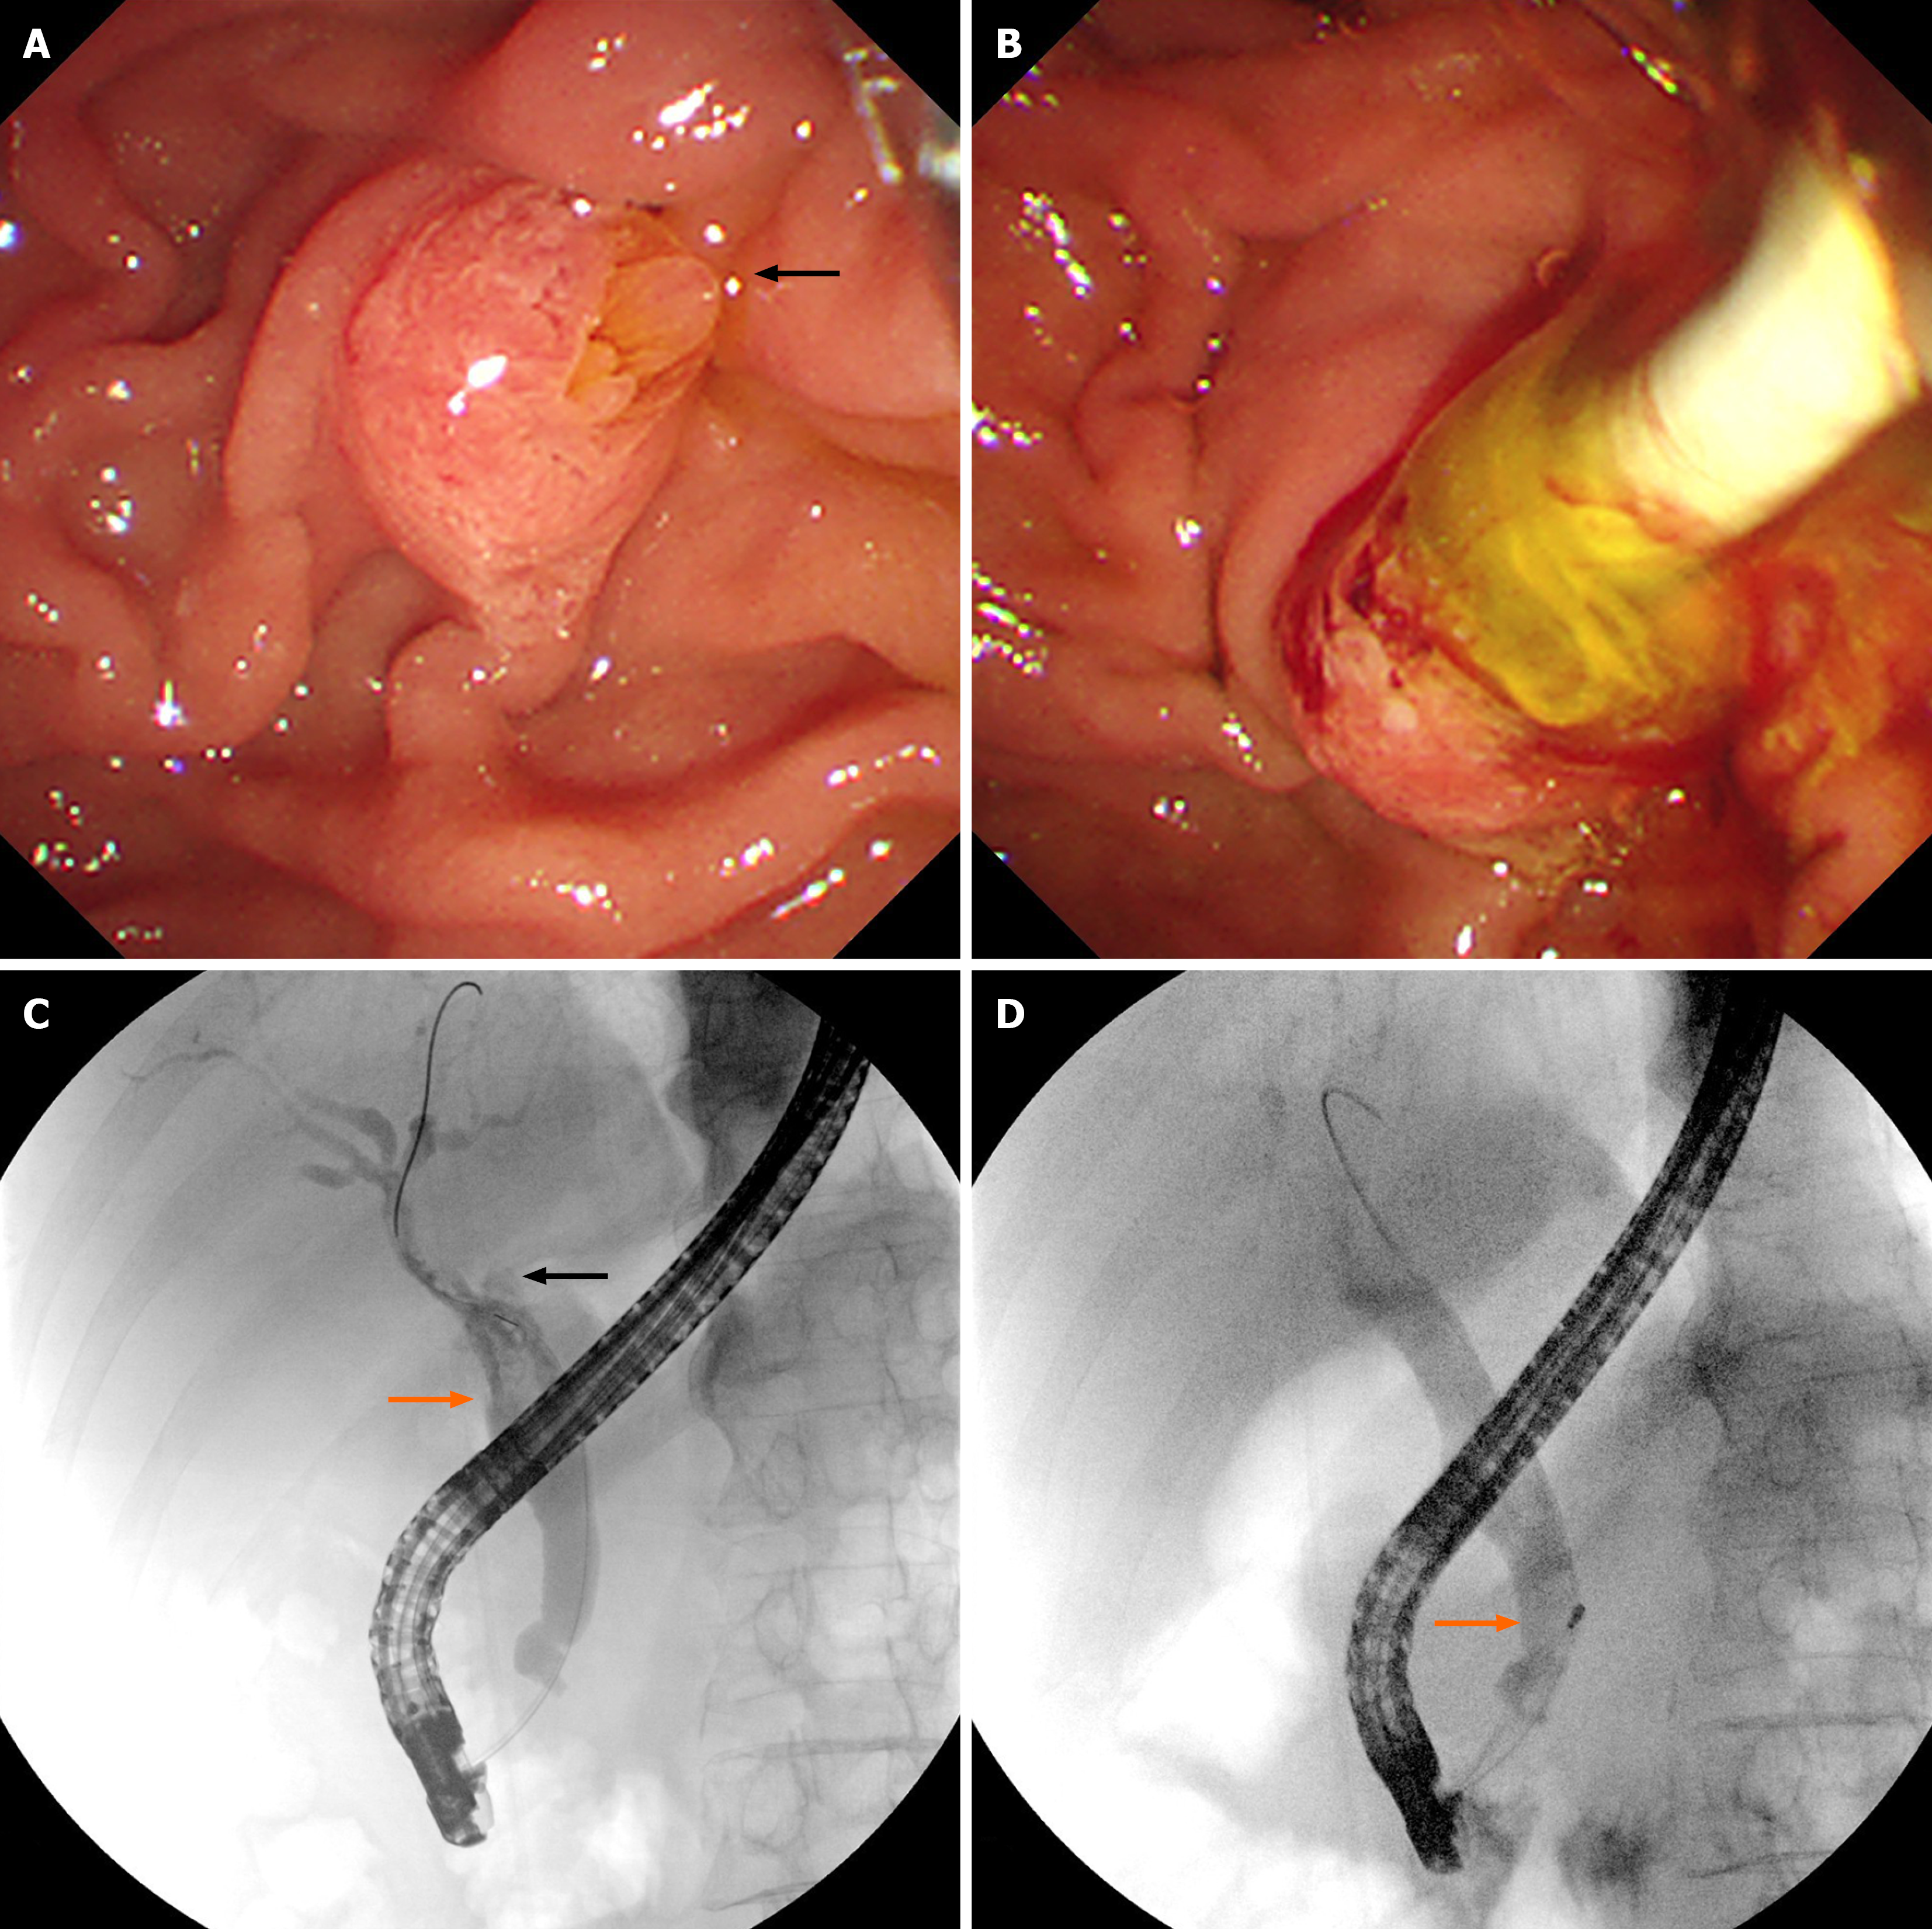

Abdominal ultrasound revealed dilatation of the common bile duct with multiple stones, dilatation of the left intrahepatic bile duct with multiple stones, adenomyosis of the gallbladder, and multiple crystals in the gallbladder. Enhanced CT images captured four years prior to admission revealed cystic dilatation of the left intrahepatic bile duct, with a size of approximately 41 mm × 22 mm, stones in the left intrahepatic bile duct, and adenomyosis at the fundus of the gallbladder (Figure 1A). MR images revealed dilatation of the left intrahepatic bile duct, local cystic dilatation, and stones in the left intrahepatic bile duct (Figure 1B-D). After admission, enhanced CT images captured in the arterial phase revealed cystic dilatation of the left hepatic duct, with a size of approximately 63 mm × 51 mm, numerous papillary nodules, stones in the left intrahepatic bile duct, and common bile duct dilatation (Figure 1E). MR images revealed cystic dilatation of the left hepatic duct with papillary nodules, stones in the left intrahepatic bile duct, common bile duct dilatation, and stones in the common bile duct (Figure 1F-H). Endoscopic retrograde cholangiopancreatography (ERCP) revealed that the duodenal papilla was enlarged and protruded into the intestinal cavity. However, there was no surface erosion and no visible tumour. The papillary orifice was significantly dilated, with a fish-mouth appearance. A large amount of translucent and jelly-like mucus was continuously oozing from the duodenal papilla. Cholangiography revealed significant dilatation of the common bile duct and multiple cloudy, irregular filling defects in the extrahepatic bile duct. During the clearing of the bile duct with the balloon catheter, the morphology and location of the filling defect in the bile duct were altered, and a large amount of translucent jelly-like mucus containing bile flowed out from the swollen duodenal papilla (Figure 2). The equipment we used was video duodenoscope (Olympus, JF-260V) and C-arm machine (GE HealthCare, OEC Elite). The wire-guided cannulation technique was selected. For this patient with IPMN-B, the papillary orifice was relatively large, making cannulation not particularly challenging. And during ERCP, a bile duct stent was placed to minimize post-ERCP cholangitis risk.

Cholangiography enables dynamic observation, and its diagnostic significance is substantial, particularly during the initial contrast study, which has the highest diagnostic value. Both ERCP and percutaneous transhepatic cholangiography (PTC) can reveal the following findings: (1) Localized bile duct strictures; (2) Segmental or diffuse biliary duct dilation; (3) Intrahepatic cystic lesions communicating with the biliary tree; and (4) Multiple amorphous, cloud-like irregular filling defects within the bile duct[12]. ERCP offers an additional advantage over PTC by allowing direct endoscopic visualization of characteristic features, such as a fish mouth-shaped, enlarged duodenal papilla and the extrusion of translucent mucin[13]. In addition, cholangiography certainly has inherent limitations. It cannot reliably distinguish bile duct stones from benign tumours and fails to delineate the precise location of small tumours, the depth of tumour invasion, or the degree of lymph node involvement. These limitations can be effectively addressed by endoscopic ultrasound (EUS) and intraductal ultrasonography (IDUS). Furthermore, peroral cholangioscopy (POCS) enables direct visualization of biliary mucosal lesions, which provides the possibility to obtain preoperative cytological specimens and tissue samples[14]. This technique is able to diagnose early-stage, neoplastic bile duct lesions[15]. Choledochoscopy using narrow-band imaging may be helpful for the observation of fine mucosal structures, resulting in diagnosis of tumor spread in IPMN-B patients[16]. Confocal laser endomicroscopy enables in vivo histological evaluation using fluorescent pigment to diagnostically differentiate between benign and malignant biliary disease[17]. As these techniques become more widely available and the survival benefits are established. In our case, ERCP demonstrated characteristic findings of IPMN-B. A notable limitation was substantial mucin obstruction in the left hepatic duct, thereby precluding adequate visualization of the dilated duct and the intrahepatic cystic lesion communicating with it. Thereby, if conditions permit, the use of POCS in the future may help overcome this limitation.